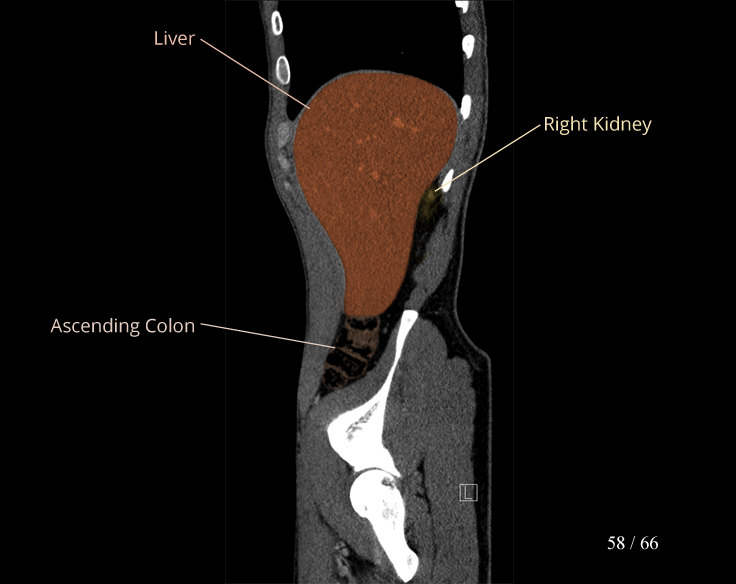

Body

Covers abdominal CT anatomy.